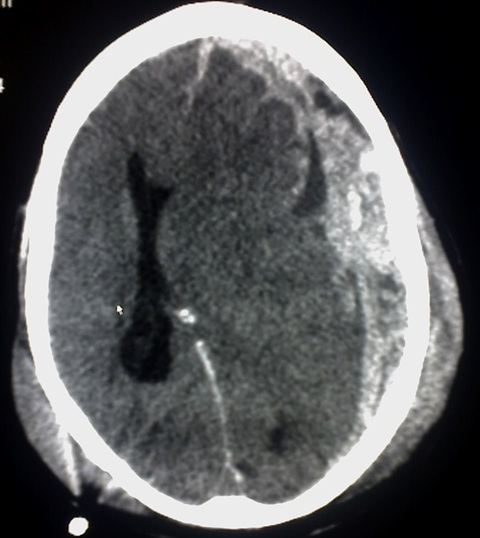

Estudio etiológico, manejo valvular y seguimiento clínico-radiológico a largo plazo.

Manejo médico y/o quirúrgico de hematoma subdural, hematoma extradural, hemorragia subaracnoídea traumática, etc, así como el seguimiento posterior.